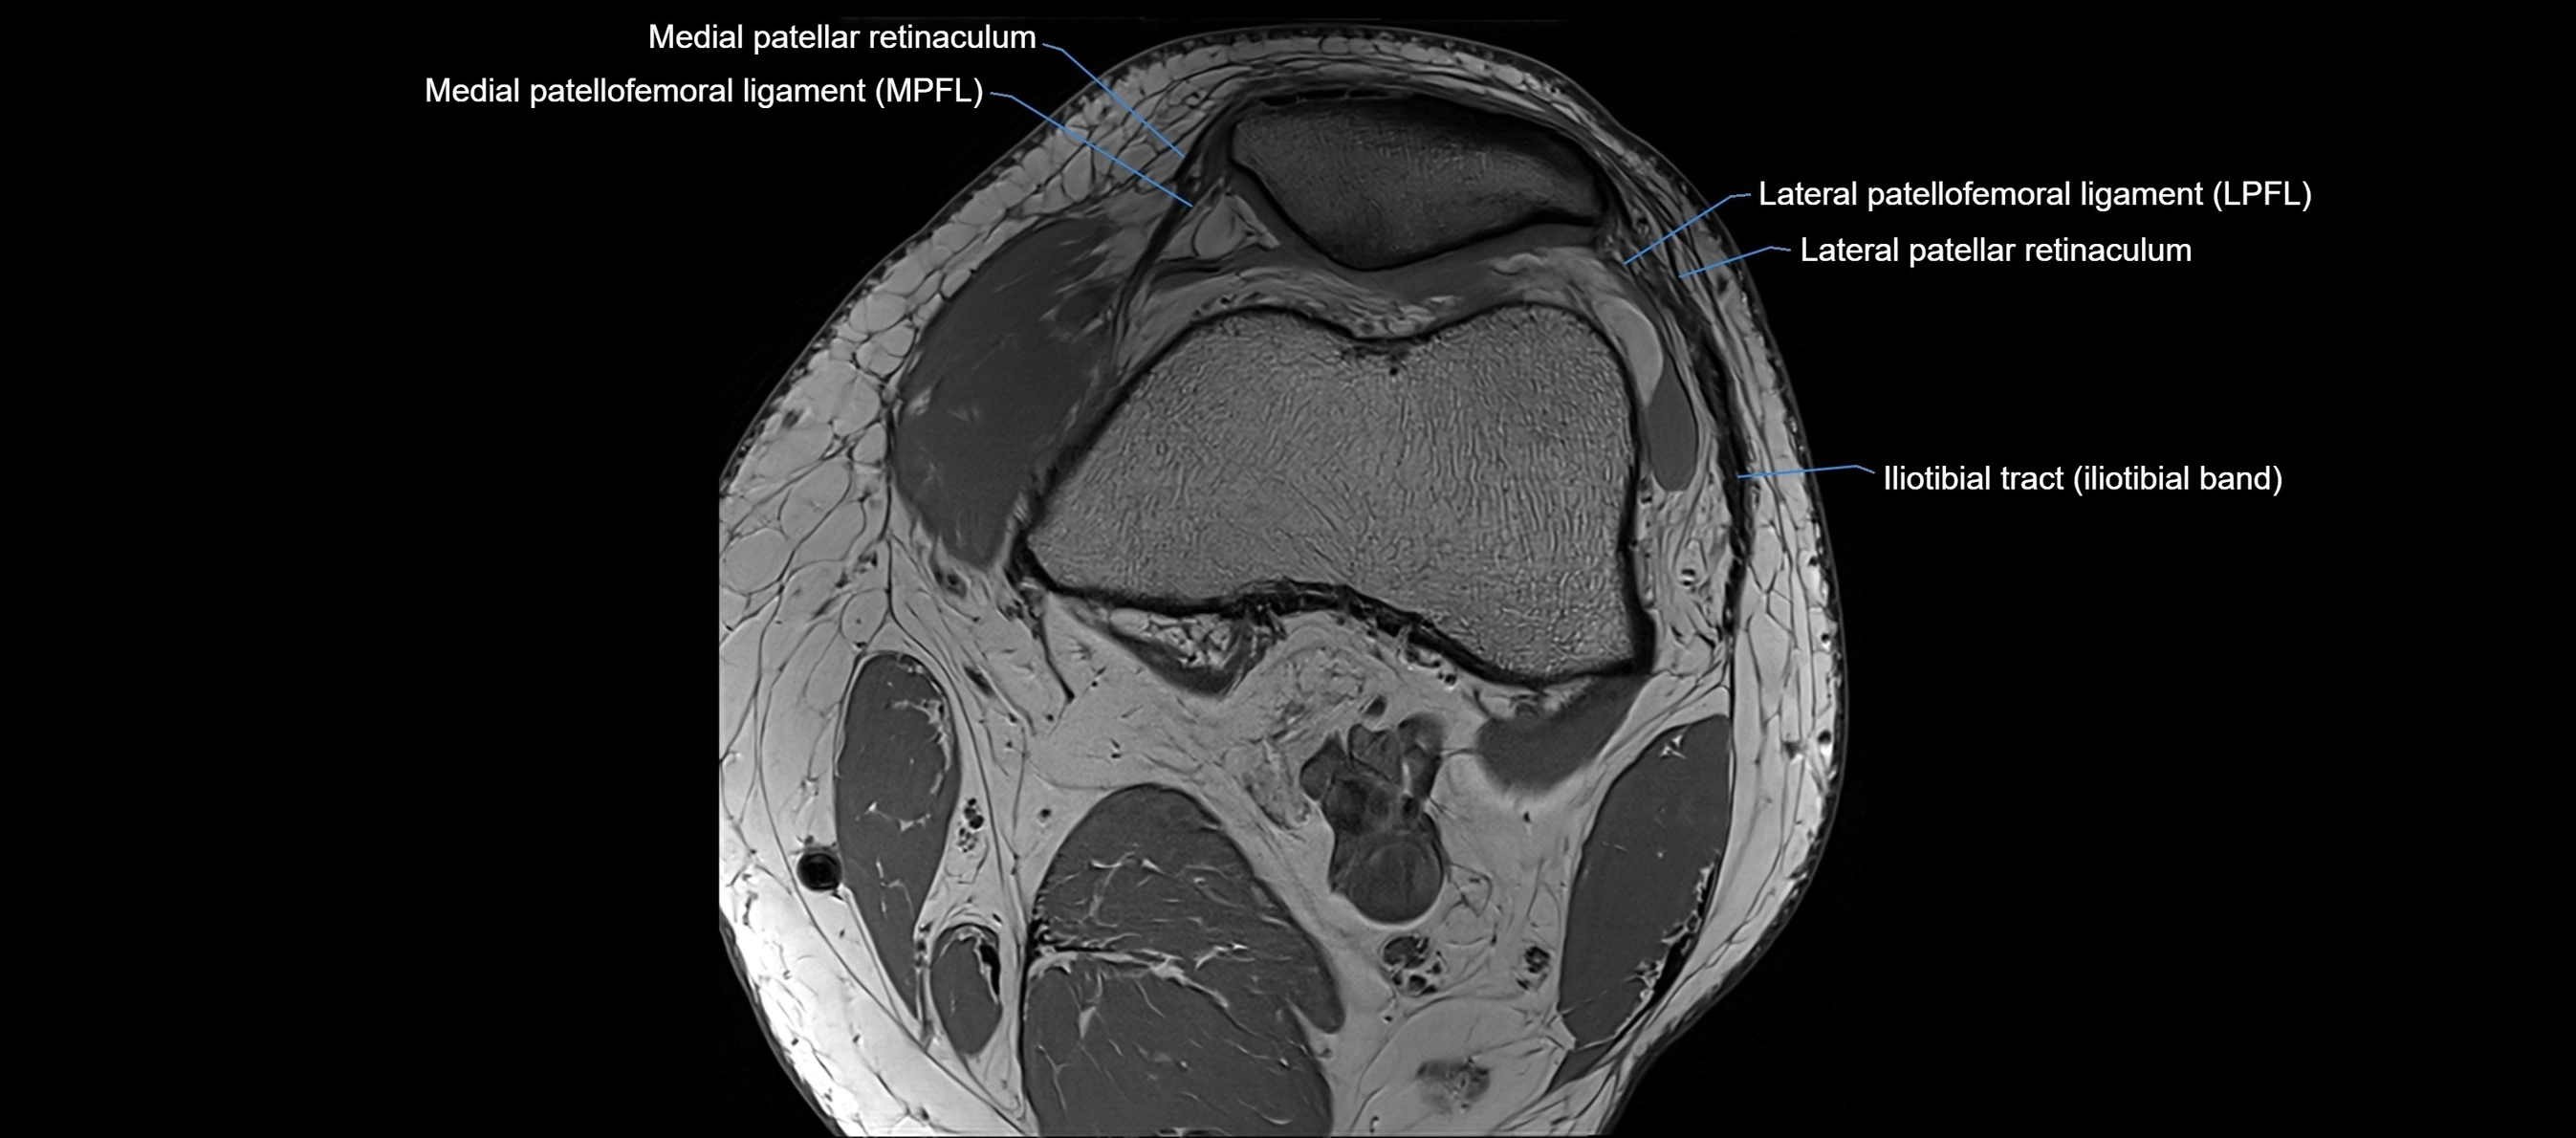

MRI images

image